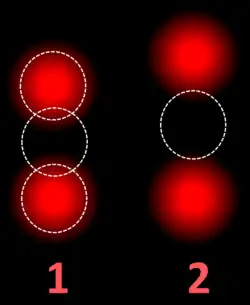

FISH can be used to measure the number of copies of the gene which are present and is thought to be more reliable than immunohistochemistry.[47] It usually uses chromosome enumeration probe 17 (CEP17) to count the amount of chromosomes. Hence, the HER2/CEP17 ratio reflects any amplification of HER2 as compared to the number of chromosomes. The signals of 20 cells are usually counted.

Two signals that are closer to each other than the signal diameter count as one. -

Algorithm for the evaluation of HER2 on fluorescence in situ hybridization (FISH).[48]

| HER2/CEP17 ratio | |||

|---|---|---|---|

| ≥2.0 | <2.0 | ||

| Average HER2 copy number per cell | ≥4.0 | HER2 positive | Additional work-up required |

| <4.0 | Additional work-up required | HER2 negative | |

- ^ a b c Diagram and table by Mikael Häggström, MD. Adapted from: Wolff AC, Hammond ME, Allison KH, Harvey BE, Mangu PB, Bartlett JM, et al. (July 2018). "Human Epidermal Growth Factor Receptor 2 Testing in Breast Cancer: American Society of Clinical Oncology/College of American Pathologists Clinical Practice Guideline Focused Update". Journal of Clinical Oncology. 36 (20): 2105–2122. doi:10.1200/JCO.2018.77.8738. hdl:1805/18766. PMID 29846122. S2CID 44143975.